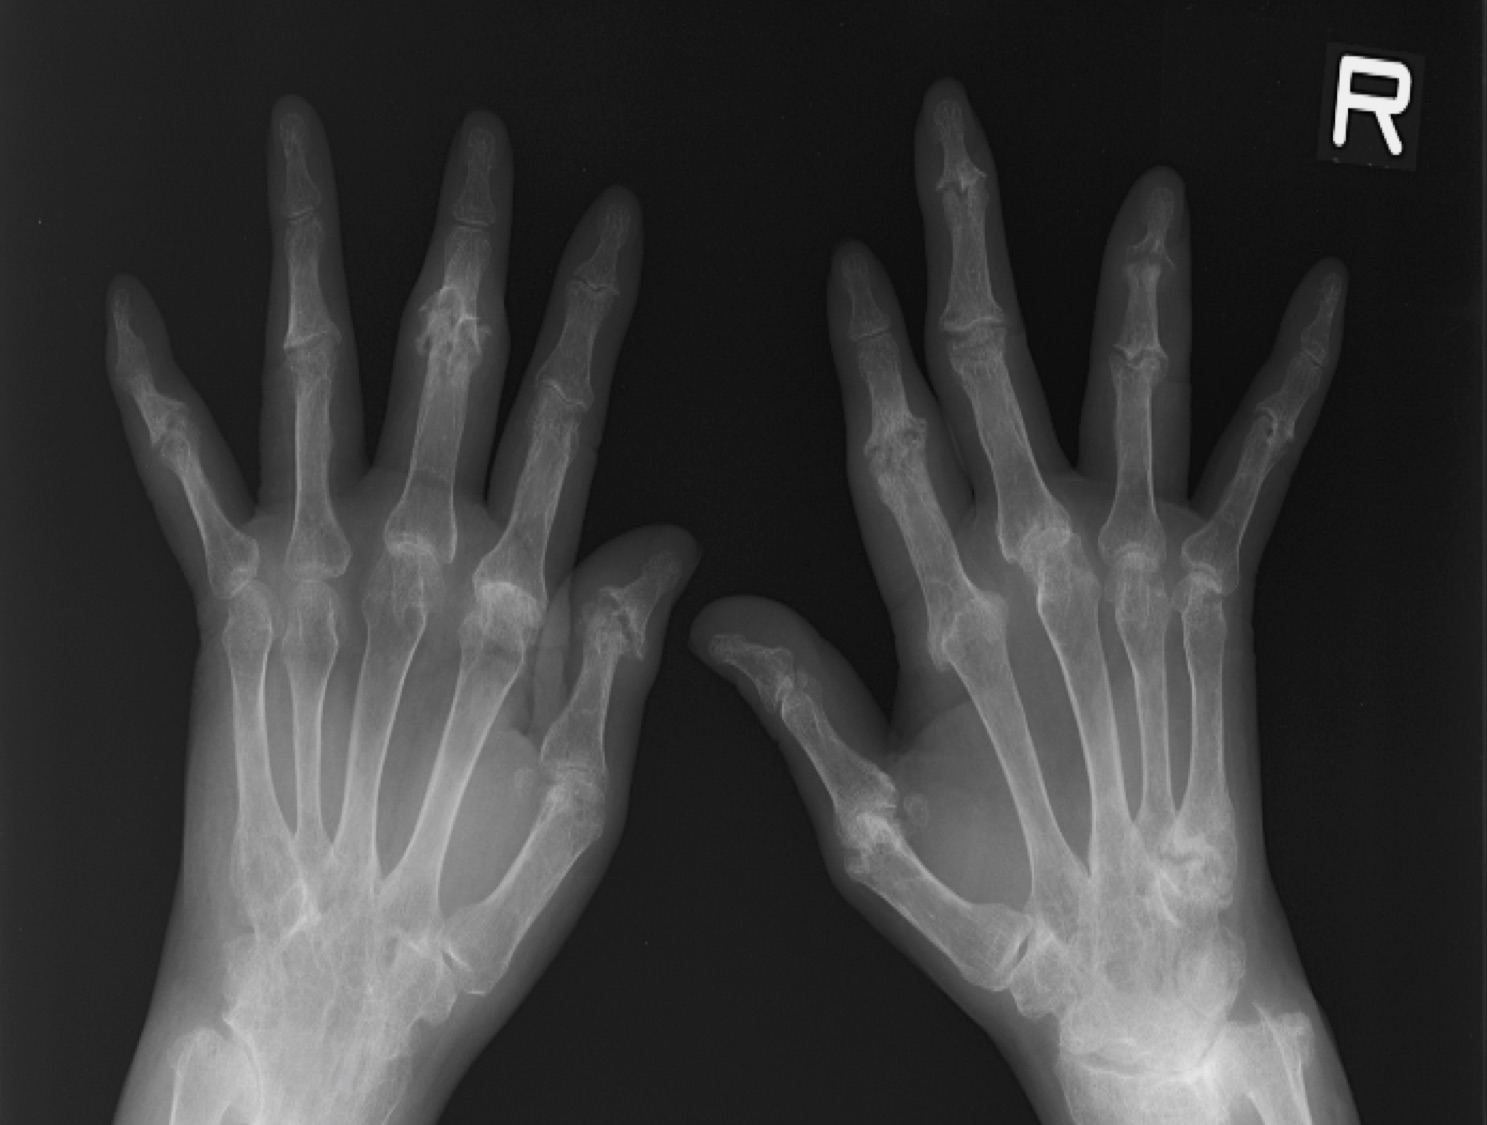

PsA が指などの小さな関節に影響を与えるのは一般的です。多くの場合、この症状は爪に最も近い関節に影響を与えます。

PsA は通常、関節に非対称的に影響を及ぼします。つまり、一方の手には発症し、もう一方の手には発症しない可能性があります。症状は軽度から重度まであり、進行したり減少したり、長期間同じ状態が続くこともあります。

PsA の後期では、軟骨の喪失により関節間の空間が狭くなったり、完全に消失したりすることがあります。

医師は、 X 線検査、超音波検査、 MRI スキャンなどの画像検査を注文することもあります。